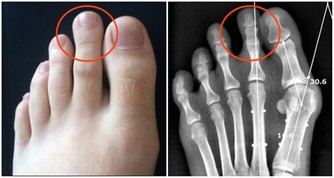

腳部出現青筋

腳面部位本來是平坦無皺紋的,如果表面出錢青筋凸起,說明腳部的血液循環開始出現受阻現象。雖然身體暫時感覺不到其他的不適癥狀,但是我們千萬不可以忽視這一癥狀。往往大病之前總是潛伏著一些小毛病。

靜脈曲張

靜脈曲張是指由於血液淤滯、靜脈管壁薄弱等因素,導致的靜脈迂曲、擴張。靜脈曲張的外在表現就是青筋暴起,並且長時間消退不了。靜脈曲張雖然聽起來可怕,但是人體並沒有其他不適,似乎不會影響正常生活,所以很多人並不重視。

其實這是非常錯誤的看法,靜脈曲張本身可能是其他病變的繼發表現,如靜脈閉塞。靜脈閉塞對身體的傷害可謂是致命性的,其對心臟的傷害可想而知